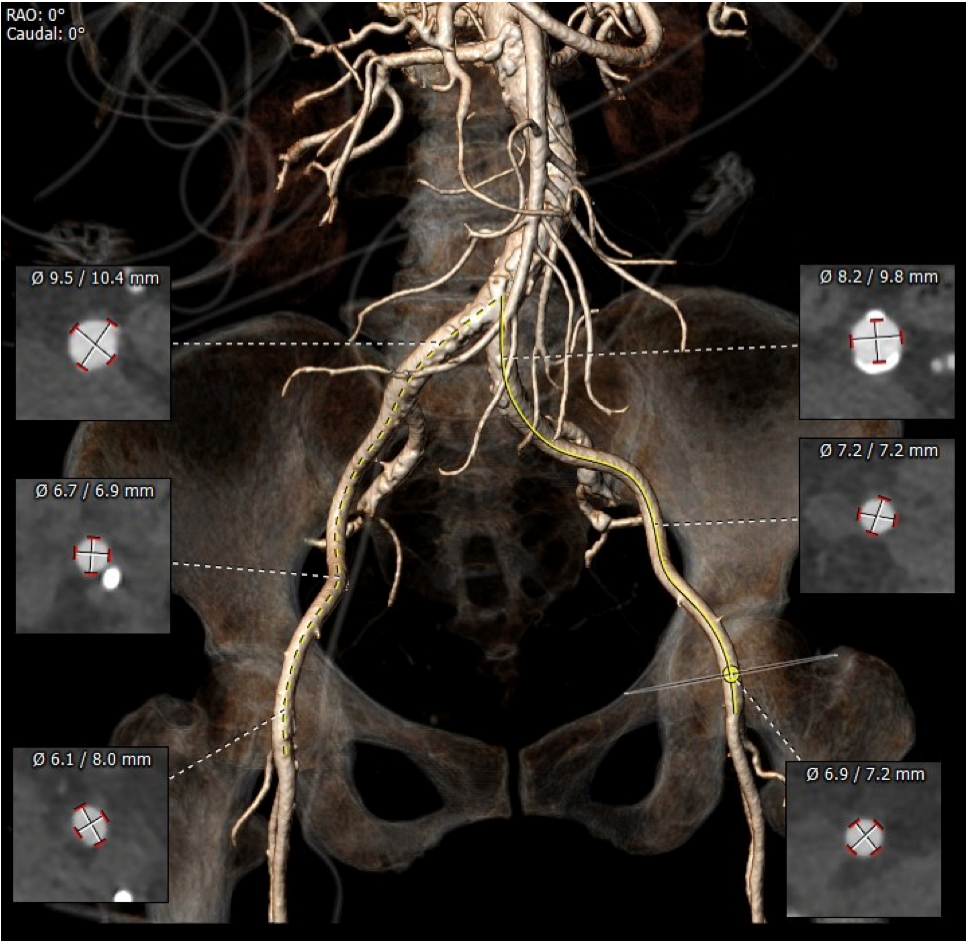

血管外周入路评估

入路血管少量钙化无其他病变,双侧血管内径良好,整体入路血管条件良好。